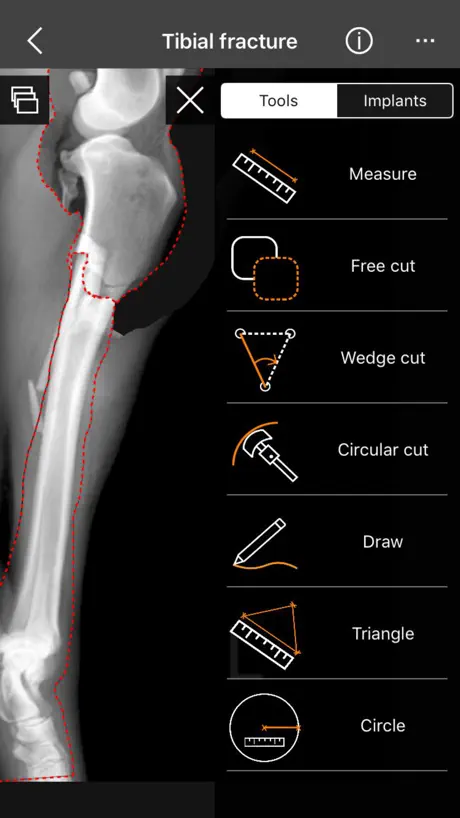

3. Tools:

a) Linear Measure.

b) Radial measure/Circle draw.

c) Angle measure/Triangle draw.

d) Free cut.

e) Wedge cut, CTWO and angular osteotomies.

f) Circular cut, TPLO.

g) Free Draw.

3. Tools:

a) Linear Measure.

b) Radial measure/Circle draw.

c) Angle measure/Triangle draw.

d) Free cut.

e) Wedge cut, CTWO and angular osteotomies.

f) Circular cut, TPLO.

g) Free Draw.